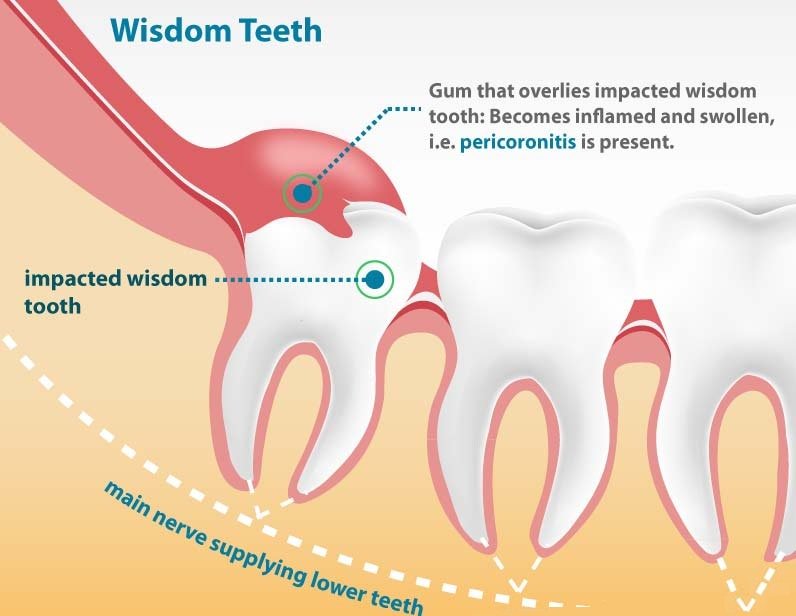

Проведите процедуру удаления под местной анестезией для минимизации боли.

После удаления зуба следуйте рекомендациям стоматолога по уходу за раной.

Избегайте жесткой и твердой пищи в первые дни после процедуры.

Принимайте назначенные обезболивающие препараты, чтобы уменьшить дискомфорт.

Регулярно полощите рот солевым раствором для предотвращения инфекции.